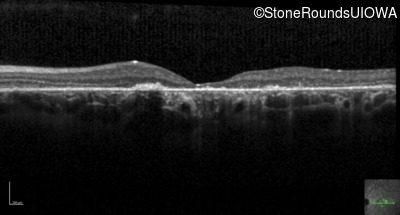

Optical Coherence Tomography - Right - 20/400 sc

Exemplar / OCT Stack

OCT Stack